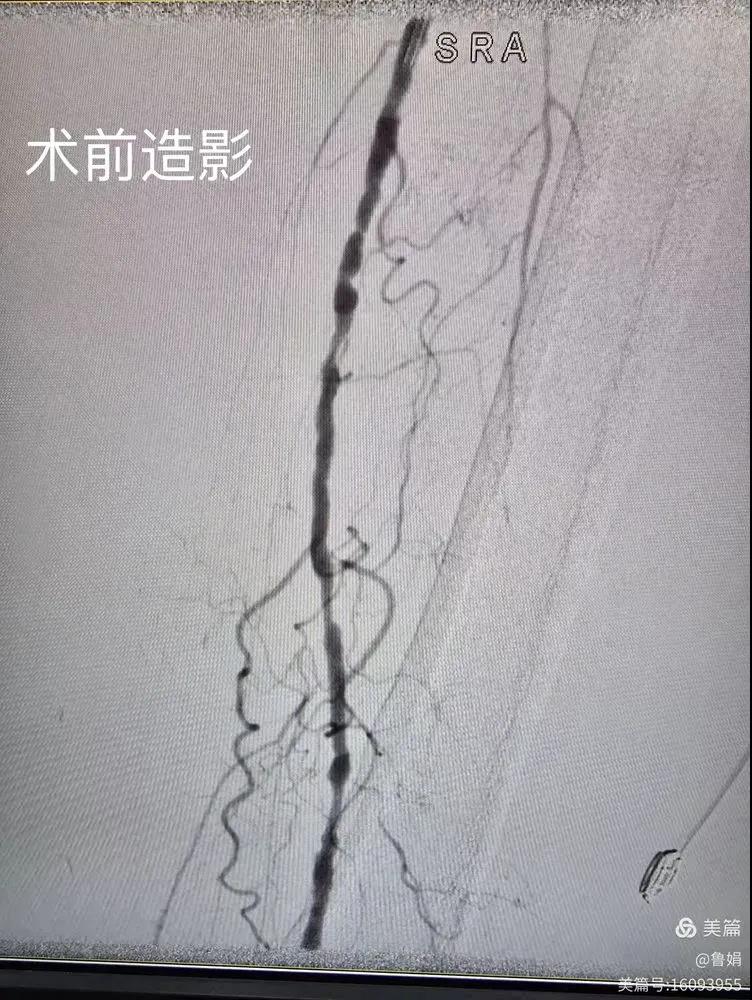

據悉,該患者,女,73歲,下肢動脈硬化閉塞癥,“以靜息痛,間歇性跛行”入院,CTA評估:股淺動脈,腘動脈間斷性多段重度狹窄,外二科血管外科團隊根據患者病情,結合檢查結果,經過科室會診后,決定對該病人行介入治療。手術由周創(chuàng)業(yè)副主任與北大一院血管外科專家郭宏杰教授聯(lián)合開展,對股淺動脈,腘動脈重度閉塞段行血管開通+藥涂球囊擴張成形,術后狹窄明顯緩解,血流恢復!

下肢動脈閉塞的介入開通是外周介入領域難度最大的技術之一,這項微創(chuàng)介入手術的開展,實現了漯河市中醫(yī)院在下肢動脈血管介入治療上零的突破,進一步推動了醫(yī)院介入治療技術的發(fā)展,讓患者足不出戶就能切實享受到優(yōu)質的醫(yī)療資源,極大方便了患者就醫(yī)。(介入中心:魯娟)